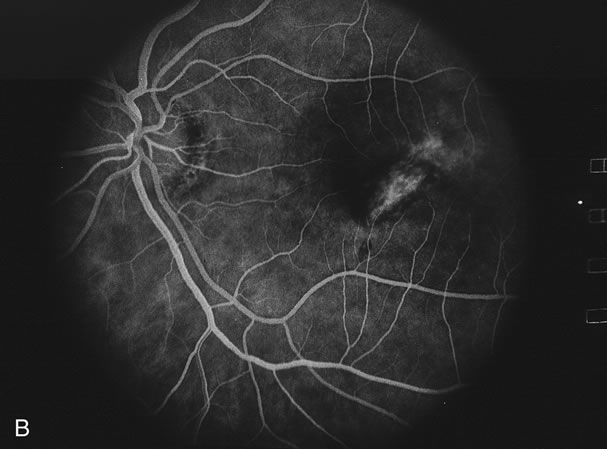

The classic findings in the acute cases are lesions of variable size that are hypofluorescent in the early phase of the fluorescein angiogram. In the late phases of the angiogram there is hyperfluorescence of the lesions. In the late phases, there also may be leakage from the disc as well, and there also may be staining of the retinal vessels because of the vasculitis. With resolution of the disease, there still may be a mottled pattern of fluorescence correlating with the areas of pigment clumping and pigment atrophy (Fig. 8).

Fig. 8. A. Early fundus angiogram showing hypofluorescence of the acute posterior multifocal placoid pigment epitheliopathy (APMPPE) lesions. B. Later stage of the angiogram showing staining of the APMPPE lesions.

Fig. 16. A. Color fundus photograph showing the jigsaw pattern of choroidal and retinal atrophy extending from the disc along the arcades. At the inferior edge of the superotemporal lesion there is a recurrence noted by the grayness of the retina. B. Fluorescein angiogram in the laminar venous phase showing a large window defect in the area of inactive choroiditis and blockage of the choroidal fluorescence in the area of active choroiditis. C. In the late phase of the fluorescein angiogram there is staining of the edges of the inactive choroiditis and marked hyperfluorescence in the area of active choroiditis.

Fig. 17. A. Classic inactive case of serpiginous choroiditis showing the jigsaw pattern of disease surrounding the fovea. B. Fluorescein angiogram showing staining of the edges of the inactive serpiginous choroiditis. There is blocked fluorescence in the areas of hyperplasia of the retinal pigment epithelium. C. Indocyanine green angiogram showing absence of fluorescence in the area of inactive choroiditis.